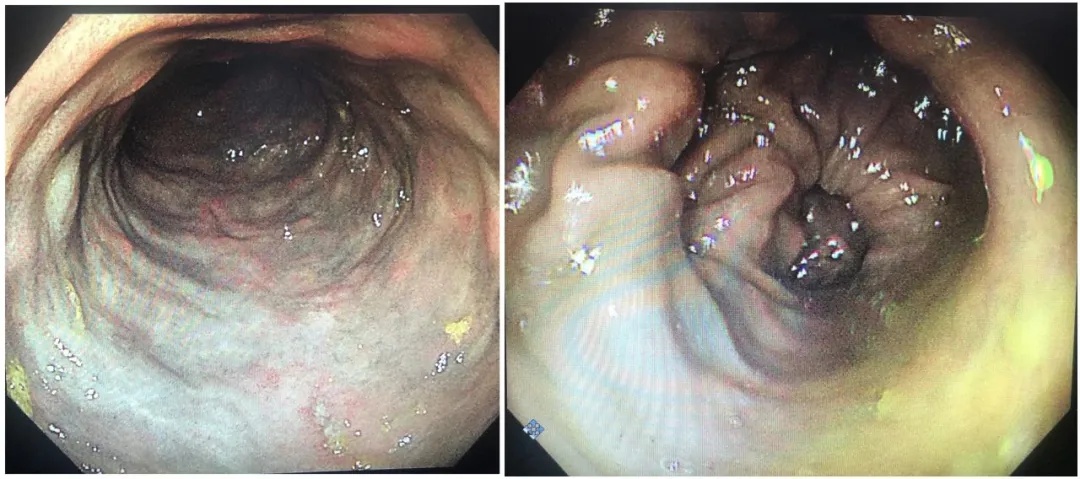

但如果喝多了,可能会带来不少问题。而在国内外文献中,均有报道长期、过量使用栀子苷可以引发特发性肠系膜静脉硬化性结肠炎。

患者集中在中国、日本、韩国等东亚国家,多有密切接触中草药栀子的病史。

此前就有52岁老刘过量饮用栀子茶,险些肠坏死,后经医生诊断为“特发性肠系膜静脉硬化性结肠炎”并已经诱发缺血性肠梗阻,老刘被收治入院接受进一步治疗。